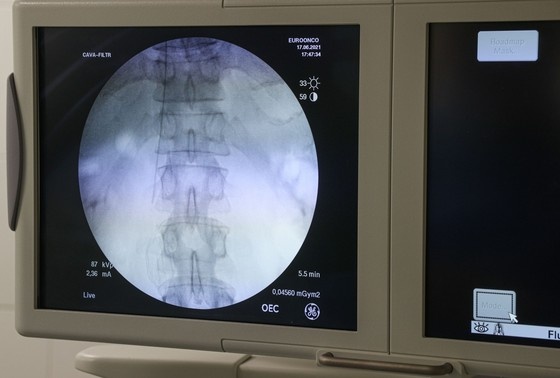

Сергей Булкин/NEWS.ru